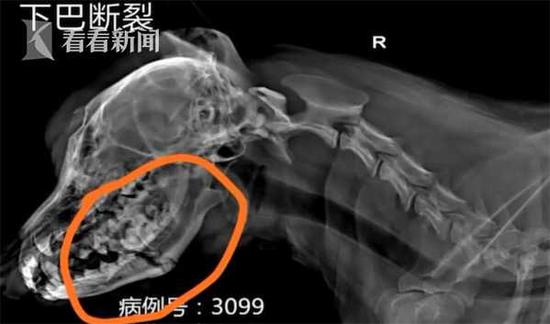

“整个下巴被打裂了,有2到3处不同时间造成的骨折,说明这个主人不止一次打狗。”

这是一只3岁的“银狐”狗,在宠物医院里,它一直闭着眼睛,动也不动,医生在给它进行B超检查,在肚皮位置剃毛,发现皮下有充血。据悉医院已发病危通知。